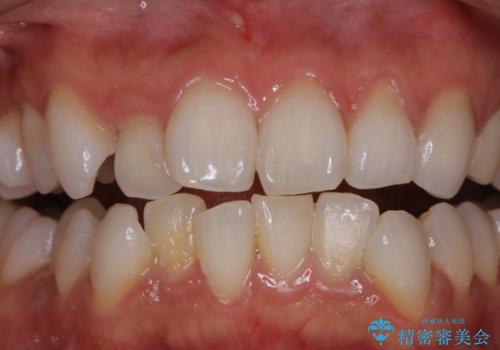

口腔内にはたくさんの細菌がいるため、ヌルヌルとしたプラーク(歯垢)が自然に歯の表面に付きます。

このプラーク(歯垢)にはたくさんの細菌が潜んでおり、虫歯や歯周病・口臭などの最大の原因です。そのため、毎日の歯磨きでプラーク(歯垢)をキレイに取り除くことが、健康な歯を保つためには欠かせません。

しかし、プラークは歯の色と似ているため、見ただけでは付着しているかどうかがハッキリとは分かりません。